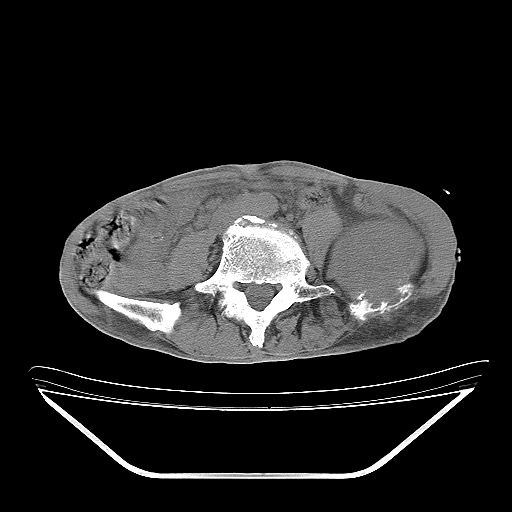

以下是引用天南地北在2007-10-4 18:01:00的发言:[br][br]考虑左髂部恶性肿瘤(溶骨性骨质破坏+软组织肿块影+残留骨质);以滑膜肉瘤可能性大。[br]建议穿刺活检

以下是引用liuyue在2007-10-4 23:38:00的发言:[br]左髂部恶性肿瘤,建议穿刺活检,或先做肺部检查,除外肺癌转移之可能。